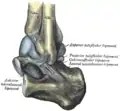

Squelette du pied, surface latérale. Capsule de l'articulation talo-crurale gauche; vue latérale

Capsule de l'articulation talo-crurale gauche; vue latérale Squelette du pied droit; vue dorsale